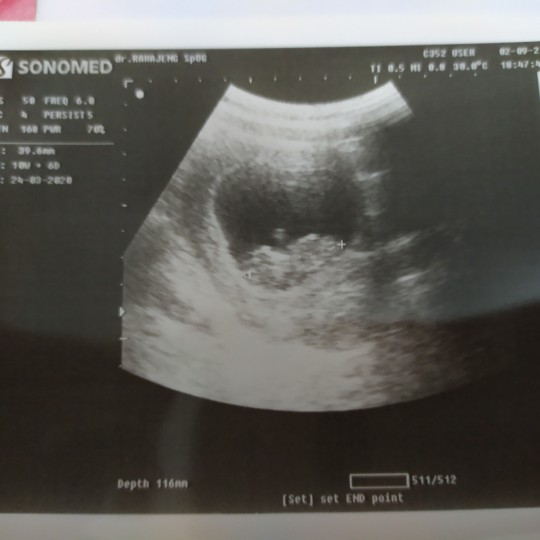

Sama bund aku juga 10W 6 D seneng banget rasanya liat jantungnya kedip2 ๐

Foto usgnya kayak aku bun 10 5 hari๐